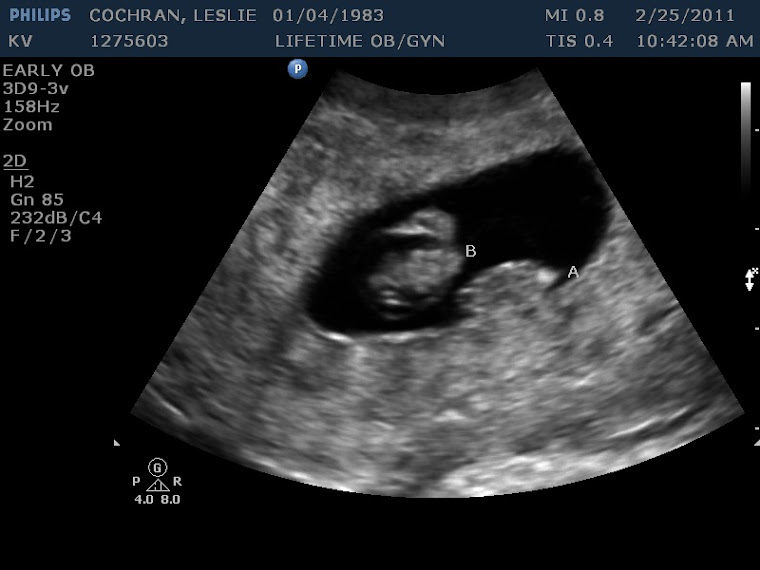

From cochranbabyaandbabyb.blogspot.com

Journey to meeting Baby A and Baby B How Do They Determine Baby A And Baby B By convention, twins are labeled as twin a or twin b at the time of birth, depending on their birth order. My babies were side by side up until about the last 3 or 4 weeks of my pregnancy. The twin assigned the title of baby a is closest to the cervix. Baby a is alway the presenting baby (the. How Do They Determine Baby A And Baby B.